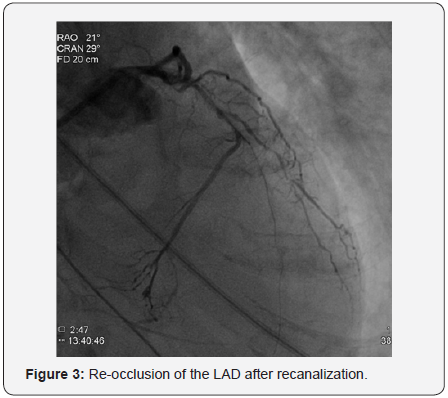

In order to perform (PCI) left trans-radial (TR) access was established then with the use of sheath-less technique seven French system (7F EBU4) (Launcher Medtronic) guiding catheter (GC) was used to engage the left main coronary artery (LMCA). A 0.014 Fielder FC guidewire (GW) was loaded on single lumen micro-catheter (MC) and was used to re-canalize CTO from mid LAD. After failure to do so using two Fielder FC guidewires, we switched to a Fielder XT-A guidewire which was successful to pass to the severely calcified mid to distal LAD with ante-grade approach. With anchoring balloon technique a 2.0x20mm Mini-Trek balloon at D2 branch at 12 atmospheric pressure unites (atm), we inflated a 1.2x6mm Mini-Trek(Abbott Vascular) balloon at 16-20atm at the CTO cap, then 2.0x20 Mini- Trek balloon at mid to distal LAD at 18-20 atm. Long dissection from very distal LAD was noted. To facilitate delivery of stents a 0.009” Rota Wire was substituted for Fielder FC to very distal LAD and rotational atherectomy (RA) de-bulking was done in a stepwise manner with 1.25 mm, then 1.5 mm burr at 180K-220K rpm as illustrated in Figures 3 & 4. We dilated the whole LAD with 2.0x20mm Mini-Trek at 20 atm then 2.5x15mm Hiryu (TERUMO) high pressure balloon (HBP) at 28 atm at proximal to mid LAD, then 3.0x15mm Hiryu HPB was inflated at p-m- LAD at 24-26 atm in order to facilitate stent passage through calcified mid LAD, subsequently we interrogated the LAD with intravascular ultrasound (IVUS) as illustrated at Figure 5.